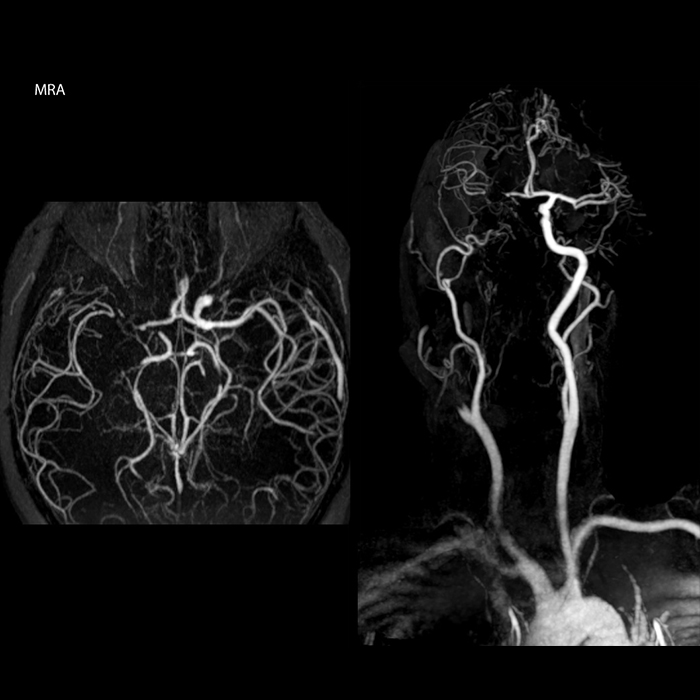

“In France, every stroke is usually imaged with MRI, not CT, even for emergency treatment.” “In France, stroke is usually imaged with MRI, not CT, even for emergency treatment. This is because MRI helps us directly visualize ischemia in the acute phase, but can also help rule out differentials such as MS and hematoma. In addition, we can assess the intracranial and extracranial vessels during the same examination,” says Dr. Savatovsky.

“Every center is different, but for me the ideal protocol for stroke includes diffusion weighted imaging, FLAIR, and fast susceptibility imaging,” says Dr. Savatovsky. “Our fast susceptibility weighted imaging takes 50 seconds, so it’s as fast as T2*-weighted imaging. It visualizes hemorrhage but also the clots. We also do 3D MR angiography that provides information on cervical and brain vessels. If the patient does not need immediate treatment, or if additional information is needed to decide on treatment, we might also add perfusion imaging and post-contrast T1-weighted imaging.”